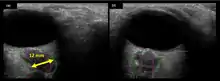

The astronauts affected by long term visual changes and prolonged intracranial hypertension have all been male, and SOS may explain this because in men, the sternocleidomastoid muscle is typically thicker than in women and may contribute to more compression. The reason that SOS does not occur in all individuals may be related to anatomic variations in the internal jugular vein. Ultrasound study has shown that in some individuals, the internal jugular vein is located in a more lateral position to Zone I compression, and therefore not as much compression will occur, allowing continued blood flow.

Intracranial pressure (ICP) needs to be directly measured before and after long duration flights to determine if microgravity causes the increased ICP. On the ground, lumbar puncture is the standard method of measuring cerebral spinal fluid pressure and ICP,[6][44] but this carries additional risk in-flight.[4] NASA is determining how to correlate ground-based MRI with inflight ultrasound[4] and other methods of measuring ICP in space is currently being investigated.[44]